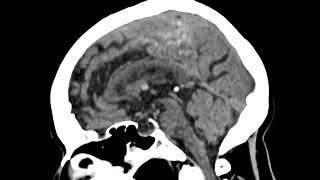

COLLOID CYST 3RD VENTRICLE NAVIGATION GUIDED MICROSURGERY -dr suresh dugani/HUBBALLI//INDIA Colloid cyst of the third ventricle

Colloid cyst of the third ventricle Resection of Colloid Cyst of the third ventricle: Minimally Invasive Surgery